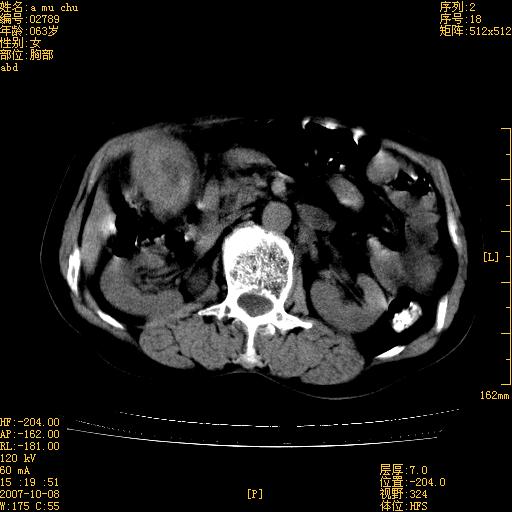

以下是引用王维浦在2007-10-17 21:02:00的发言:[br]胆囊增大,囊壁明显不规则增厚,邻近肝组织浸润,肝内外胆管无扩张。诊断:胆囊ca;[br]胰头软组织肿块影,考虑是由转移肿大的胰后淋巴结、没有肠道准备的十二指肠及胰头共同形成。[br]

以下是引用zhangzexing在2007-10-18 7:13:00的发言:[br]支持胰头占位,慢性胆囊炎. 2.肝左叶前外侧段占位,血管瘤?建议增强

以下是引用影像实习生在2007-10-17 19:49:00的发言:[br]支持胰头占位,慢性胆囊炎. 2.肝左叶前外侧段占位,血管瘤?建议增强.

以下是引用刘振江在2007-10-17 19:42:00的发言:[br]没有增强,胰头癌?胆囊及肝左叶占位?